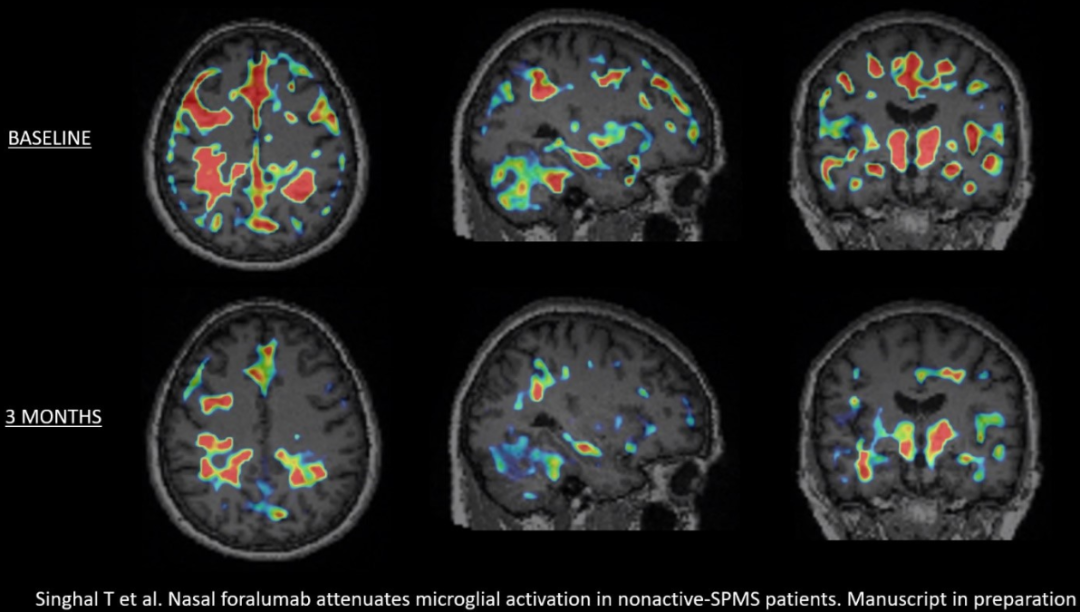

此前,Tiziana在6名鼻内 Foralumab 扩大使用的非活动性SPMS患者中,3个月内观察到5名小胶质细胞活化减少。